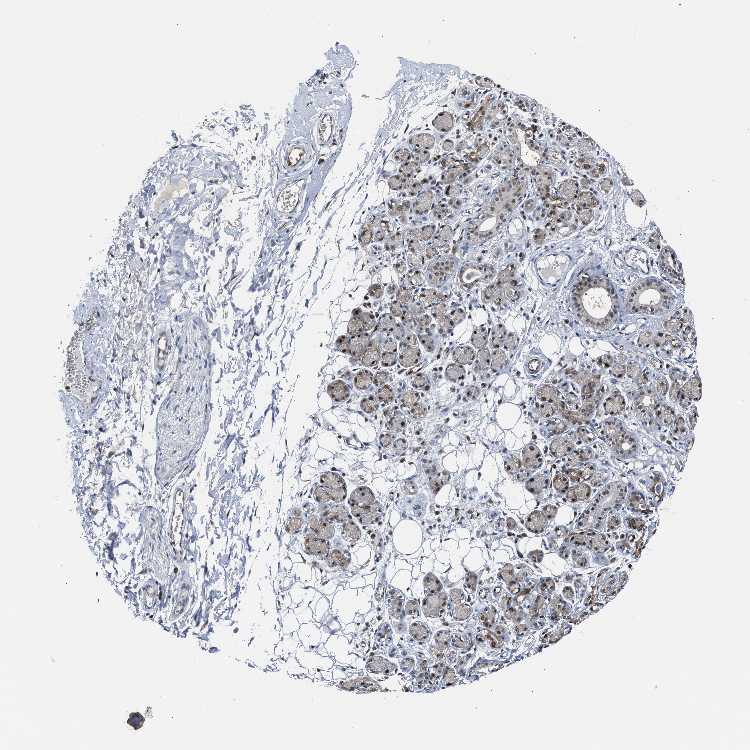

ADIPOSE TISSUE - Antibody stainingi

Antibody staining in the annotated cell types in the current human tissue is reported as not detected, low, medium, or high, based on conventional immunohistochemistry profiling in selected tissues. This score is based on the combination of the staining intensity and fraction of stained cells.

Each image is clickable and will lead to virtual microscopy that enables deeper exploration of all samples and also displays staining intensity scores, fraction scores and subcellular localization as well as patient and tissue information for each sample.

Antibody HPA019878Antibody HPA020096

Adipocytes MediumNot detected